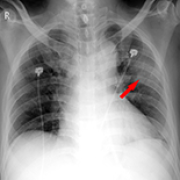

14 Sep 2021 : Database Analysis

Chest Radiological Findings and Clinical Characteristics of Laboratory-Confirmed COVID-19 Patients from Saudi Arabia

Rowa Aljondi, Salem Alghamdi, Abdulrahman Tajaldeen, Ikhlas Abdelaziz, Lubna Bushara, Hind A. Alghamdi, Hassan Alhinishi, Bandar Alharbi, Raied Alshehri, Abdullah Aljehani, Mansour Almotairi

DOI: 10.12659/MSM.932441

Med Sci Monit 2021; 27:e932441

3,434 1,332 0

3434 1332 0